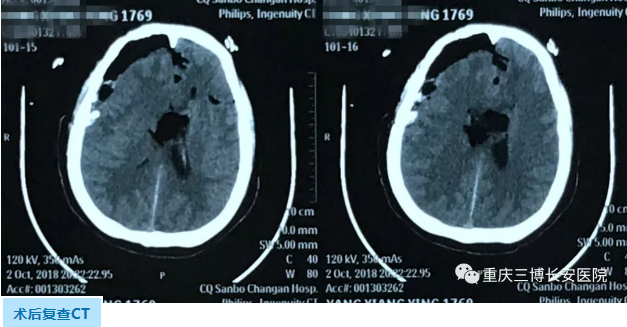

NO.2右额颞开颅右颞叶及胼胝体肿瘤切除术

打开硬脑膜,见脑压高,术中探查见:右侧颞叶病变,肿瘤组织稀软,质韧,与周围正常脑组织无明显界限,血供中等,病灶呈囊实性,囊液呈黄色,显微镜下肿瘤切除满意,术域彻底止血,继在额部中央前回前方皮层造瘘直达第二处肿瘤,切除胼胝体处肿瘤,肿瘤镜下全切,术域彻底止血。

术后患者恢复清醒,复查CT肿瘤切除满意。